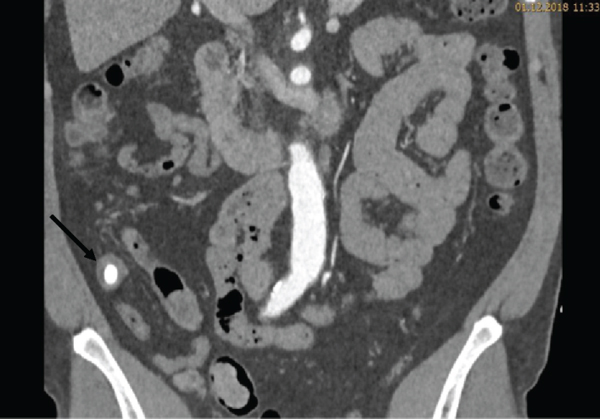

During the ICU stay, the patient’s condition was stable. Bed rest was prescribed, and strict blood pressure control was performed with continuous intravenous infusion of labetalol and urapidil targeting a systolic blood pressure below 120 mmHg. Oral antihypertensive treatment with nebivolol, moxonidine, and amlodipine was started. Continuous labetalol and urapidil infusions were stopped on day three. Due to hypokalemia, potassium chloride tablets were prescribed. Five days after admission, another CT angiography was performed to review the development of the hematoma. The CT scan revealed a reduction of the hematoma. Furthermore, in the arterial phase, a faint hyperdense lesion (max. 348 HU (Hounsfield units), ) was detected in the posterior fundus of the stomach (Figures 1(a)–1(c)). The previously acquired native scan was performed only for the thorax and did not include the stomach; therefore, it was not possible to determine with certainty whether the lesion reflected contrast media extravasation or foreign material. However, due to the intramural hematoma of the descending aorta, the possibility of an aorto-gastric fistula was considered. Additional measurements of hemoglobin were performed to screen for relevant bleeding. As the patient’s hemodynamics as well as hemoglobin levels remained stable, no further investigations (e.g., gastroscopy) were undertaken and our strategy remained expectative. At the same time, we were searching for an alternative clarification of the findings. We found that (1) the patient had ingested two potassium chloride tablets five hours before the CT scan, (2) potassium chloride tablets have radiopaque properties [1, 2], and (3) there were other hyperdense but sharply demarcated structures in the stomach and in the small bowel (density max. 1724 HU) (Figures 2, 3(a), and 3(b)). After putting all available information together, we suggested that the radiopaque lesion in the stomach was caused by the remnants of a degrading potassium chloride tablet ingested by the patient hours before the CT investigation whereas the other potassium chloride tablet ingested at the same time had been propulsed to the small bowel without being degraded in the stomach.

(a)

(b)